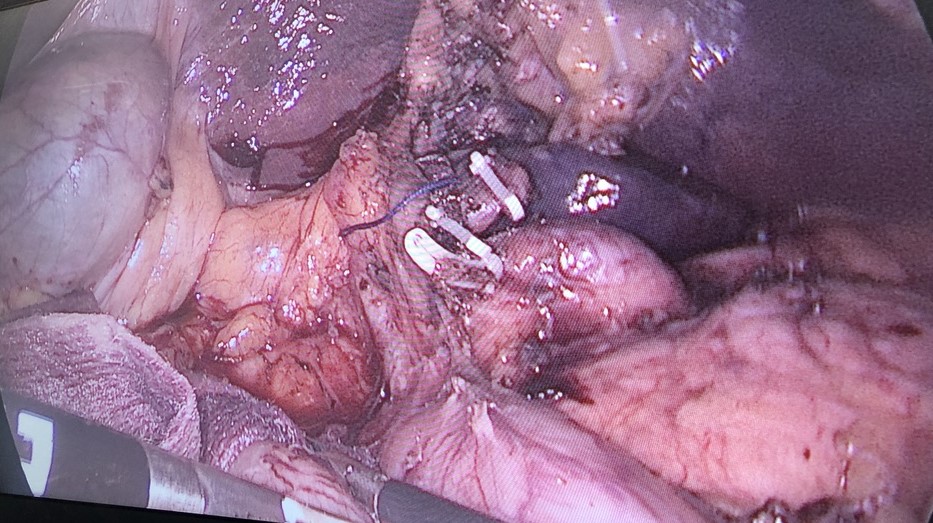

Cắt gan trái nội soi do ung thư đường mật trong gan